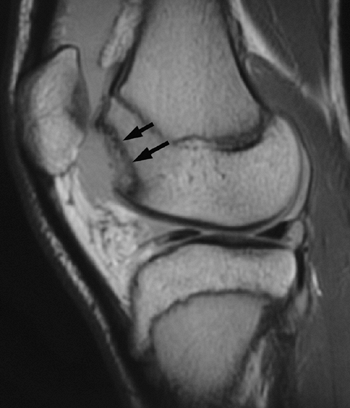

accompanies an acute patellar dislocation. Plain radiographs,

specifically anteroposterior, lateral, and Merchant view (also known as

skyline views) should be carefully

evaluated for patellar reduction, lateral tilt, and osteochondral

fracture. The Merchant view is an axial view of the patellofemoral

joint with the knee flexed to a consistent 35 to 45 degrees (41) (Fig. 32.1).